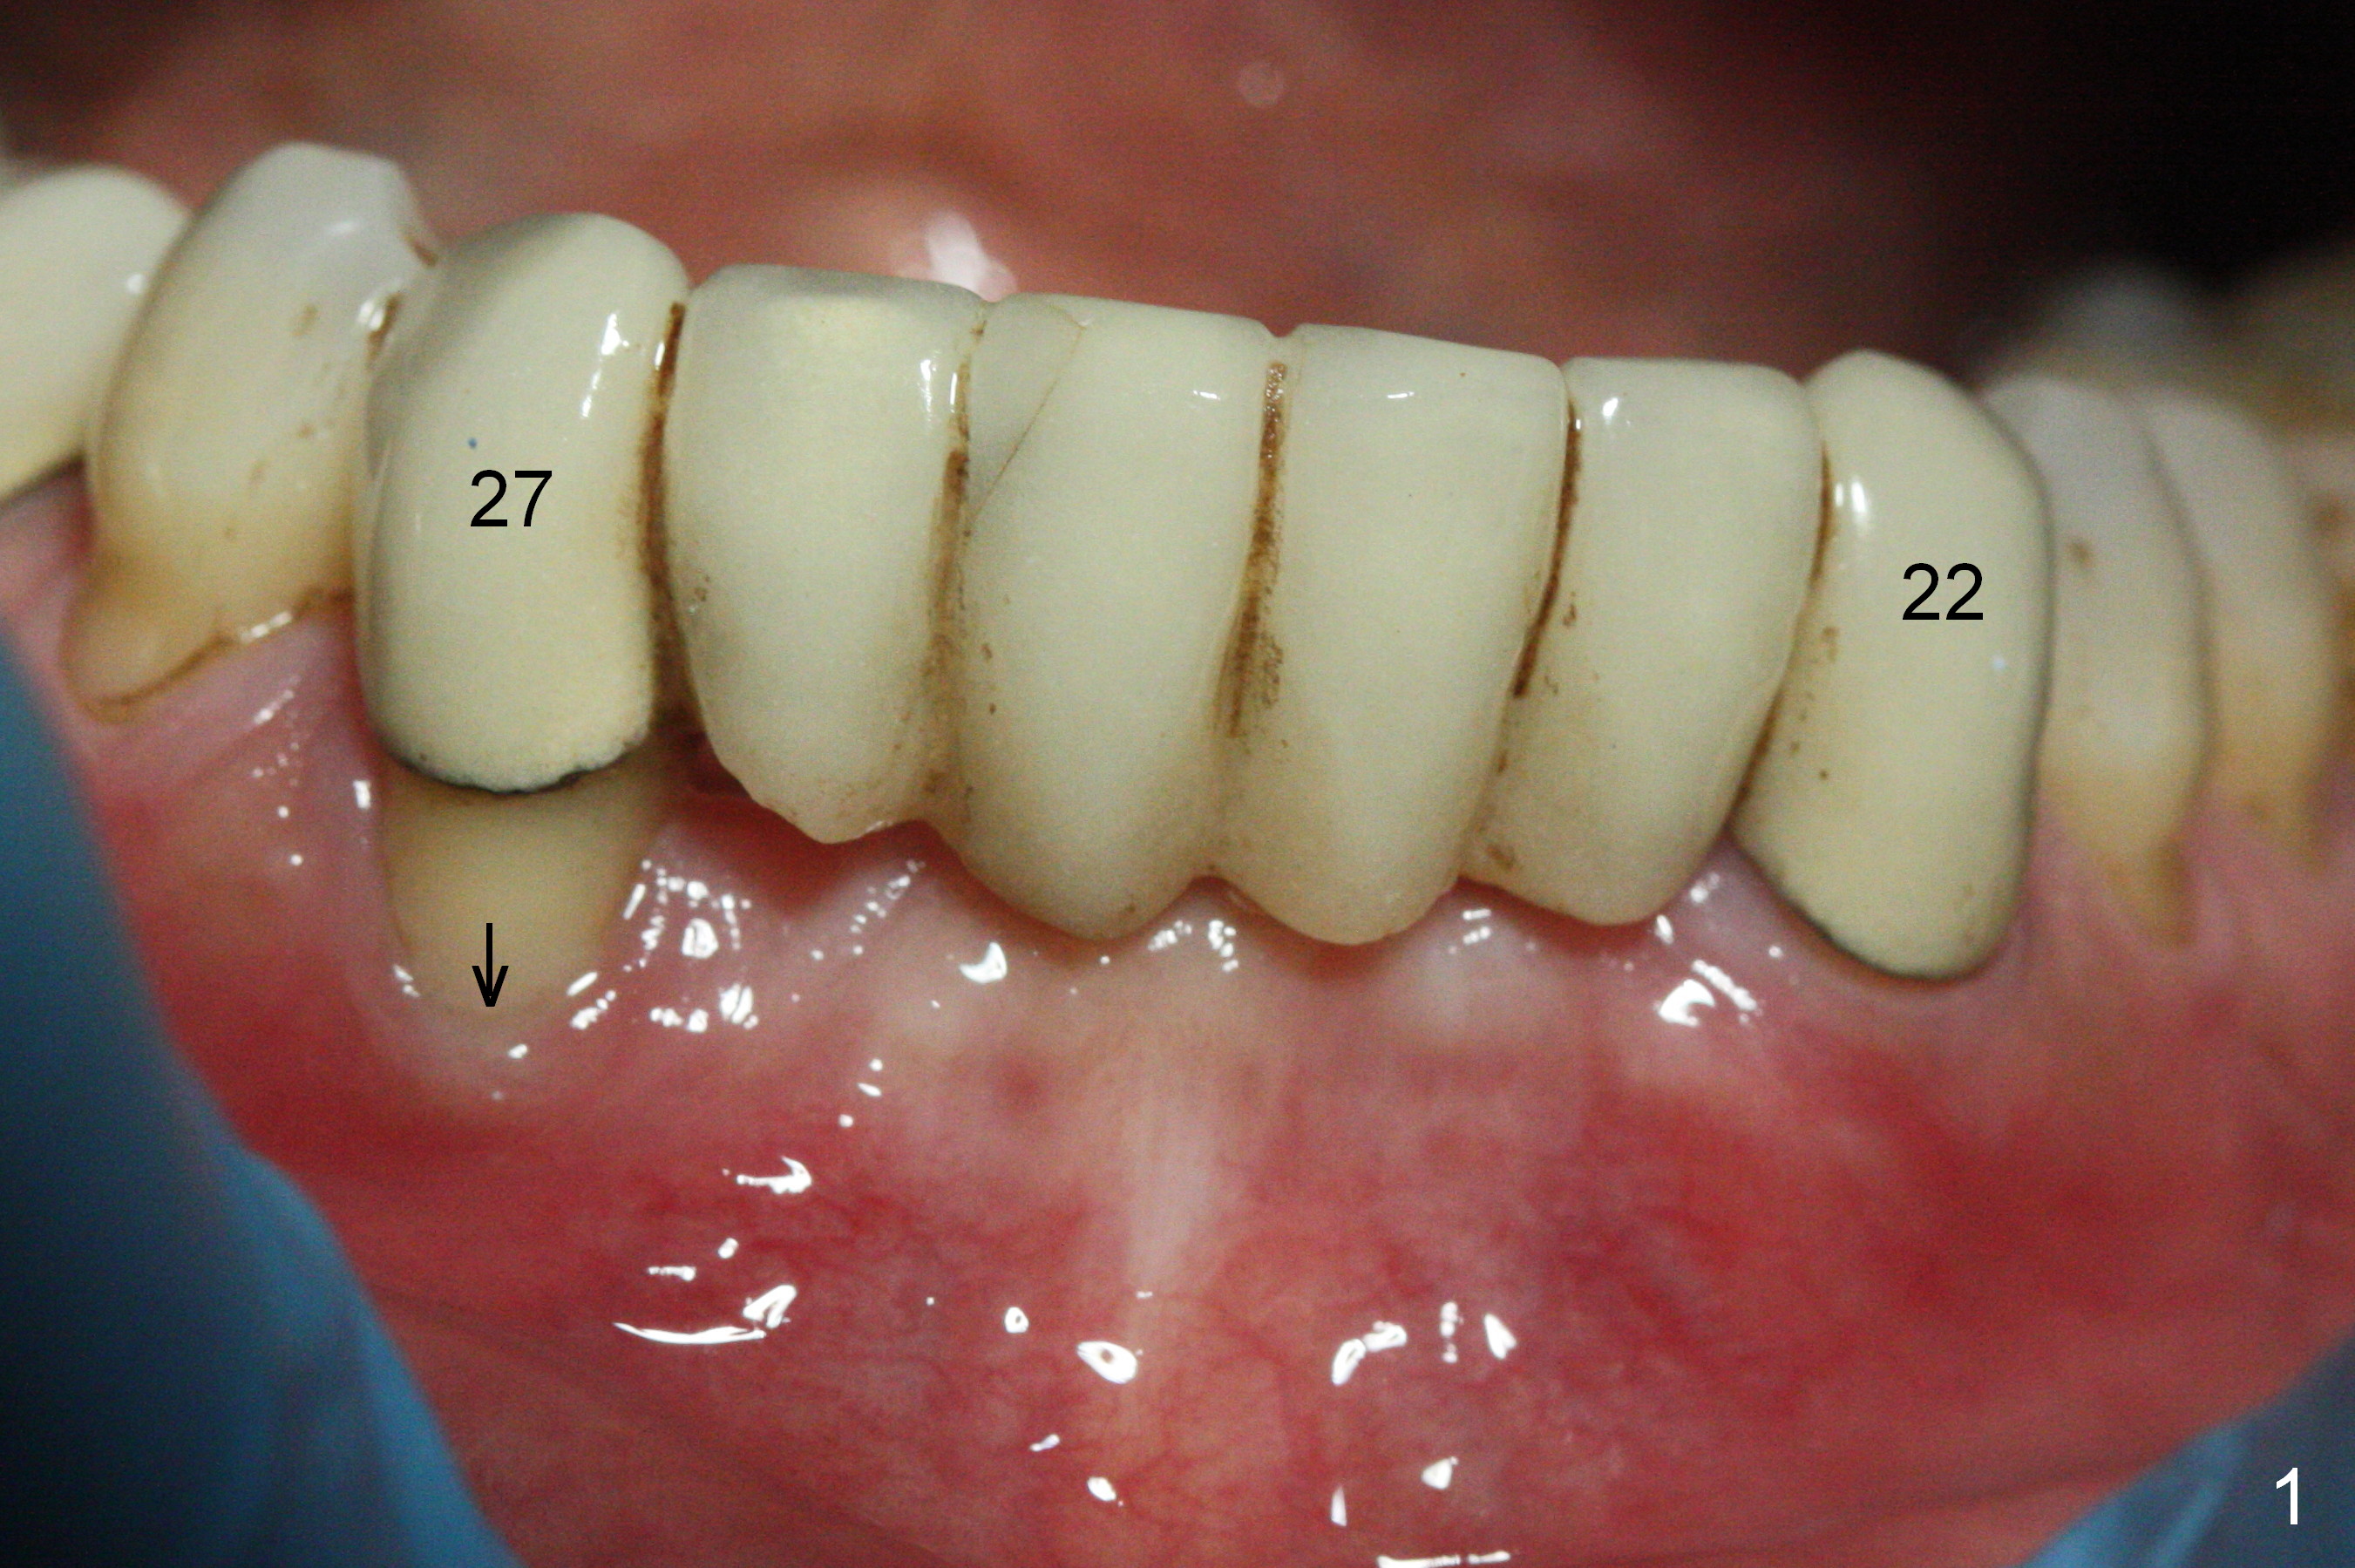

There is severe buccal gingival recession at #27 (Fig.1 arrow), as compared to that at #22. After removing the bridge and extraction of #27 (Fig.2 with severe loss of the buccal plate), a 3x18 mm drill is used to finish osteotomy (Fig.3). A 3.8x13 mm UF implant (Fig.3 green line) will be placed with 9 mm in the apparently solid, native (new) bone (blue line), while the coronal 5 mm will be occupied by the 5 mm cuff of a cemented abutment (pink line). The white dashed line is the gingival margin. The osteotomy is initiated as lingual as possible so that there will be at least 2 mm buccal gap when the narrow implant is placed. In spite of effort and precaution (guided surgery could control the trajetory), the coronal end of the implant tilts buccally so that a 4.5 mm 15 ° A 4 mm angled abutment is placed slightly subgingival (except buccal; Fig.5 A).